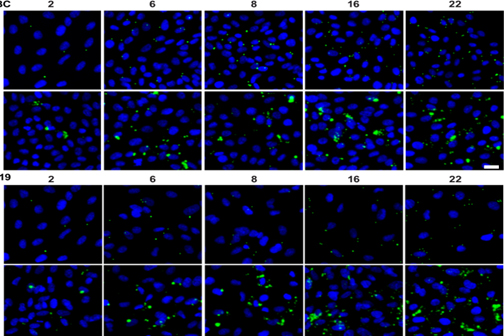

LSU Health New Orleans Develops New Human Cell Line to Study Blinding Eye Disorders

Under the direction of Boyd Professor Nicolas Bazan, MD, PhD, scientists at LSU Health New Orleans Neuroscience Center of Excellence have developed a new, experimental human cell line from retinal pigment epithelial cells. Called ABC, these cells so closely resemble and retain the properties of native retinal pigment epithelial (RPE) cells, the research team has shown that they are a reliable cell system to study retinal degenerative diseases. More